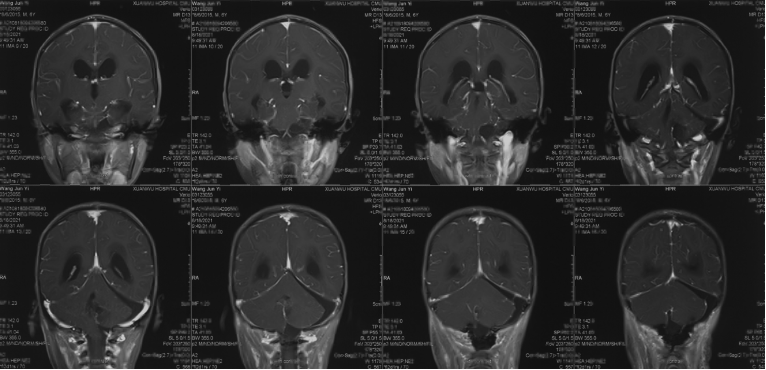

Pre-operative imaging

Preoperative enhanced MRI